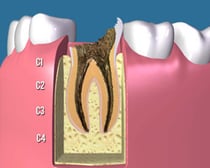

C3:

c3

かなり虫歯が進行してしまって、歯の神経と呼ばれる歯髄にまで虫歯が達してしまった状態です。熱い物で痛みが出たり、場合によってはひどくズキズキ痛むことも少なくありません。

この場合、歯を大きく削って歯の神経を除去する難易度の高い根管治療や大きく歯を削ってすっぽりかぶせる治療が必要になり、その後多くの場合はかぶせ物で修復することになります。

C4:

c4

虫歯によって、歯の頭の部分がほとんど崩壊してしまった状態です。残っている歯根の状態によっては抜歯になることも多くあります。歯を残す場合も、難易度の高い根管治療が必要で、歯根に深く維持を求める「差し歯」になります。治療後も「差し歯」によって歯根が割れるリスクが残ります。